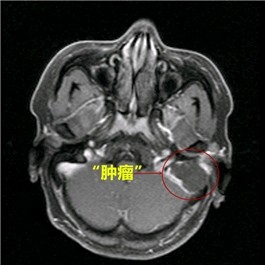

从李先生的CT片子可以见到其左侧中耳乳突巨大软组织影,并有周围骨质破坏,乙状窦前壁和天盖已不完整,部分颅脑组织都受到了挤压,提示“肿瘤”已经破坏周围骨质了,结合患者病史、体征及相关检查,考虑胆脂瘤型中耳炎可能,由于位置特殊,同时伴有骨质破坏、缺损,周围有重要的结构,如乙状窦、硬脑膜、颅脑、面神经等,如颅内留置了一颗“不定时炸弹”,疾病若进一步发展,李先生便有相关颅内、颅外并发症发生的风险,严重时甚至致命。

得知病情严重,李先生立刻入院治疗,在加强抗感染同时,完善颅脑MR、鼻内镜、耳内镜、听力学等检查,幸运地是,虽然“肿瘤”巨大,但颅脑MR示硬脑膜尚完整,且患者目前并没有面神经受损麻痹的面瘫症状,这些为手术创造了有利条件。